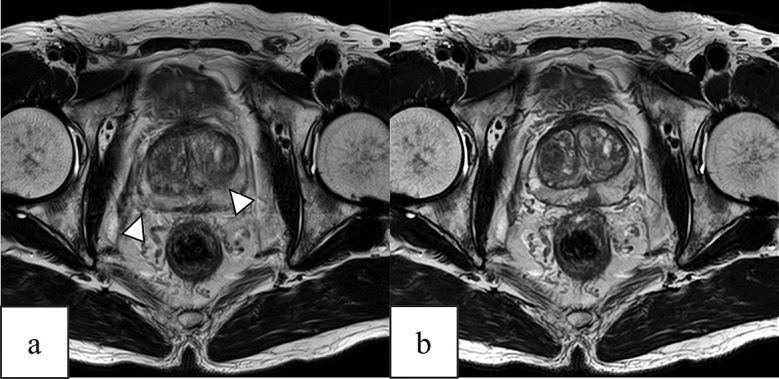

We compared the qualitative and quantitative quality of prostate conventional T2-weighted imaging and T2-weighted imaging with deep-learning reconstruction. Patients with suspected prostate cancer undergoing magnetic resonance imaging between April 2022 and June 2023 were included. Quantitative analysis was performed to determine the signal-to-noise and contrast ratios of the perirectal fat tissue, internal obturator muscle, and pubic tubercle. Eight periprostatic anatomical structures, overall image quality, and motion artifacts were evaluated by two radiologists using 5- or 4-point scales. Qualitative analysis results were compared to determine the agreement between the two radiologists. In total, 106 patients (mean age: 71 ± 8.3 years; 106 men) were included in this study. The acquisition time for conventional T2-weighted imaging and T2-weighted imaging with deep-learning reconstruction was 4 min and 16 s and 2 min and 12 s, respectively. The signal-to-noise ratio of the perirectal fat tissue and internal obturator muscle and contrast ratio of fat/muscle and bone/muscle determined via T2-weighted imaging with deep-learning reconstruction were significantly superior to those determined via conventional T2-weighted imaging (both p < 0.01). Compared with conventional T2-weighted imaging, T2-weighted imaging with deep-learning reconstruction showed significant improvement in the visualization of the periprostatic anatomy, overall image quality, and motion artifacts (both p < 0.05). Compared with conventional methods, T2-weighted imaging with deep-learning reconstruction facilitated the acquisition of good-quality magnetic resonance images of the prostate within a shorter acquisition time. T2-weighted imaging with deep-learning reconstruction will aid clinicians in diagnosing prostate cancer with shortened acquisition time while maintaining quantitative and qualitative image properties.